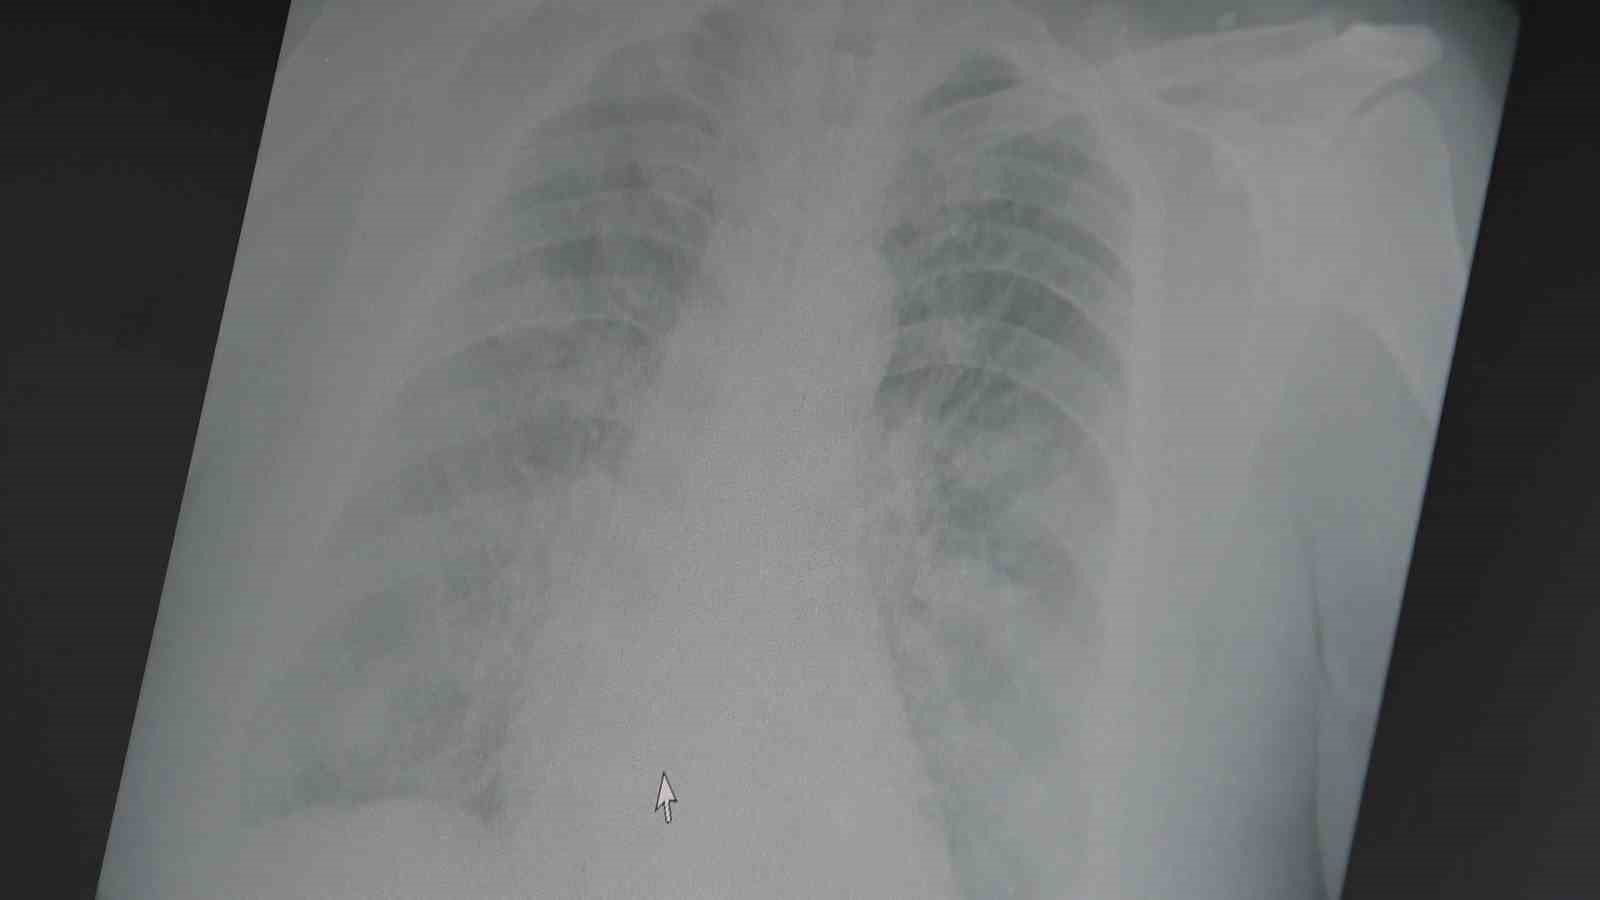

Yeni suşun A H3N2 tipi olduğunu ve kolay yayıldığını belirten Prof. Dr. Özkaya, "Her ne kadar grip aşılarının koruyucu etkinliği azalmış olsa da, ciddi hastalık ve ölümleri önlemede aşının önemi sürüyor. Grip aşısı yaptırmak hâlâ değerli" dedi.